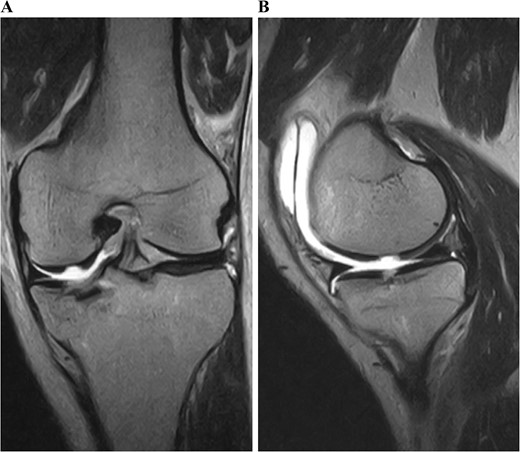

Postoperative MRI at 1 year after the surgery showed that the transplanted cultured cartilage had successfully integrated without any delamination (Fig. 6). A second-look arthroscopy was performed to evaluate the condition of the transplanted cartilage while removing the plate. The cartilage defect of the medial femoral condyle was covered by hyaline cartilage-like tissue. The depressed articular surface of the medial tibia plateau was smooth without stepping off (Fig. 7). One year after the surgery, the patient resumed daily life and sports activities without any complaint. The patient’s range of motion of the knee was full, and Lysholm’s knee score was 95.

Postoperative T2-weighted fat-suppressed magnetic resonance images at 1 year after surgery. The transplanted cultured cartilage was successfully integrated without any delamination.